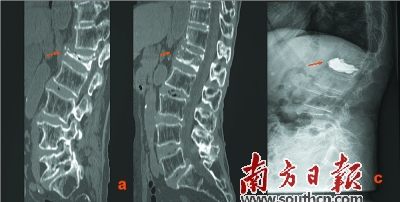

治療前后對比:a為治療前,b為手法復位后,c為手法復位+PKP術后。

梁木榮說:“該患者年紀大、腰椎壓縮程度重,受壓縮的椎節被壓扁得只剩下1/4,極大地增加了該手術的難度,很多醫生都措手無策。”而胡方煜醫生卻具有豐富的臨床經驗,他采取了中西醫結合的辦法,先對患病椎體行手法復位,復位成功后,再進行PKP手術。

胡方煜介紹:“特別嚴重的患者,椎體壓縮的程度大,椎體后壁不完整,這對手術有很大挑戰,椎體后壁不完整易造成水泥滲漏,手術具有一定的難度和風險。因此,我科采用中醫手法復位、聯合PKP手術的方法,先對病人受傷的椎體部位進行手法復位,椎體牽開整復后再進行骨水泥注入,使一些重度胸腰椎骨折患者也能完成手術治療。”